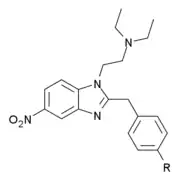

Benzimidazoles

Structures

| Benzimidazoles | ||||

|---|---|---|---|---|

|

|

|

|

|